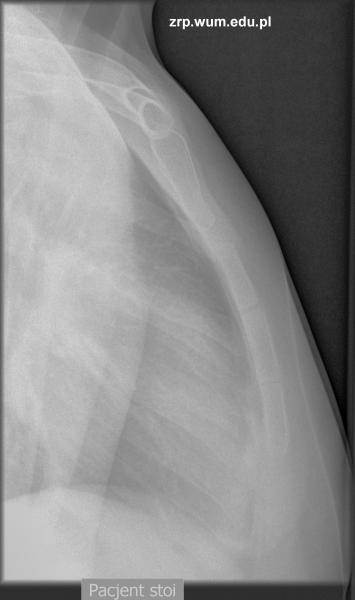

Przypadek 31: 14-letni pacjent, w trakcie przewlekłej sterydoterapii z powodu zespołu nerczycowego, zgłosił się do IP z powodu urazu okolicy mostka w trakcie ćwiczeń fizycznych. Od tej pory zgłasza ból tej okolicy.

Rozpoznanie: W badaniu RTG uwidoczniono złamanie dolnej częsci rękojeści mostka - widoczne ugięcie przedniej krawędzi rękojeści (biała strzałka). Poza tym widoczne prawidłowe jądra kostnienia mostka (czarne strzałki).